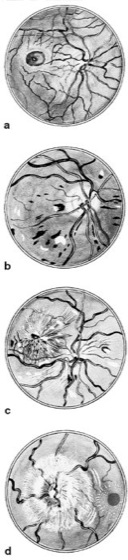

Abb. 4:Augenhintergrund:a normaler Augenhintergrund; b Augenhintergrund bei Zuckerkrankheit, c bei Nierenerkrankung, d bei Sehnervenschwellung (Hirntumor, Hirnhautentzündung u.a.)

Linsenauge, konvergent entstandenes Lichtsinnesorgan von Höheren Schnecken (z.B. Weinbergschnecke) und Kopffüßern (Ausnahme: Nautilus) sowie Wirbeltieren (einschließlich Mensch), sekundär auch bei Gliederfüßern ( vgl. Infobox ). Bei diesen Tieren ähneln sich die Linsenaugentypen in ihrem funktionellen Aufbau, sind phylogenetisch jedoch unabhängig voneinander entstanden. Die Neuerung gegenüber dem Lochkamera-Auge (Nautilus;Kameraauge) besteht in der Linse, die eine lichtstarke und gleichzeitig scharfe Abbildung im Auge ermöglicht. Das Linsenauge kann einen Durchmesser von bis zu 40 cm erreichen (bei Tiefsee-Tintenfischen). – Das Linsenauge der Kopffüßer besitzt sehr viel Ähnlichkeit mit dem Fischauge ( vgl. Abb. 1 ), es gibt jedoch einige grundlegende Unterschiede zum Wirbeltierauge. Bei den Kopffüßern stellt die Linse eine cuticulare Ausscheidung der vorderen Wand der Augenblase sowie der ursprünglichen Epidermis dar. Sie ist zweigeteilt und als Anpassung an das Leben im Wasser, wie die Fischaugenlinse, rund und mit einem zur Peripherie hin schwächer werdenden Brechungsindex versehen. Die Regenbogenhaut (Iris) geht bei den Kopffüßern aus einer Epidermisfalte hervor. Die Hornhaut (Cornea) legt sich als eine durchsichtige Hautfalte über die Irisfalte. Bei den Kopffüßern wird die Netzhaut (Retina) vom hinteren Teil einer von der Epidermis abgeschnürten Blase gebildet. Somit richten die Sehzellen ihre rezeptiven Außenglieder nach der dem Licht zugewandten Seite (everses Auge). Die Retina des Tintenfisch-Linsenauges gleicht in ihrem Aufbau den Retinulae der Ommatidien des Komplexauges (Farbtafel). In diesem Fall aber verschmelzen die Rhabdomere von je 4 Sehzellen zu einem Rhabdom. Durch die Anordnung der Mikrovilli in den Rhabdomeren können Kopffüßer mit ihren Linsenaugen polarisiertes Licht wahrnehmen (Polarisationssehen). Es gibt nur einen Rezeptortyp, so daß die Kopffüßer überwiegend farbenblind sind. Als Sehpigment (Augenpigmente, Sehfarbstoffe) findet man vor allem das Rhodopsin, daneben seltener das Retinochrom. Die Linsenaugen der Kopffüßer besitzen wie die Wirbeltiere äußere Augenmuskeln. – Das Linsenauge der Wirbeltiere (Auge) schnürt sich als optische Vesikel aus dem Neuralrohr zur Oberfläche hin ab, wobei sich die darüber befindliche Ektodermschicht zur Linse differenziert (Induktion [Farbtafel], Plakoden). Die nach außen liegende Schicht der Vesikel stülpt sich danach ein und bildet den Augenbulbus (Augenbecher). Die Retina und das diese umgebende Pigmentepithel entwickeln sich als becherförmige Vorstülpung des Zwischenhirns, so daß die Sehzellen dem Pigmentepithel zugekehrt und damit vom einfallenden Licht abgewandt sind (inverses Auge). Das Linsenauge der Wirbeltiere besteht aus dem nahezu radiärsymmetrischen Augapfel, der äußeren Augenmuskulatur sowie als Schutzeinrichtung bei vielen Wirbeltieren dem Augen-Lid (an dessen Rand vielfach Haare [Augen-Wimpern] sitzen) und der Tränendrüse. Das menschliche Linsenauge ( vgl. Tab. ) wird durch 6 äußere Augenmuskeln bewegt, deren motorische Nervenfasern über 3 Hirnnerven (III. [Oculomotorius], IV. [Trochlearis] und VI. [Abducens]) zu den blickmotorischen Erregungszentren im Hirnstamm ziehen. Die 3 Augenmuskelpaare sorgen für eine Bewegung des Augapfels um alle 3 möglichen Drehachsen und für eine Konvergenzbewegung, z.B. bei sich nähernden Objekten (Entfernungssehen). Es gibt mehrere Formen von Augenbewegungen, wie z.B. die kleinen, unwillkürlich auftretenden Mikrosaccaden oder die Saccaden (Blicksprünge; Bildwahrnehmung; vgl. Abb. 2 ) oder die glatten Folgebewegungen. Als Nystagmus bezeichnet man eine Mischform zwischen der langsamen, glatten Folgebewegung und den schnellen Saccaden. In den Tränendrüsen wird ständig Tränenflüssigkeit produziert, die ein Ultrafiltrat der Blutflüssigkeit (Blut) darstellt. Durch den Lidschlag wird diese ständig gleichmäßig auf Hornhaut und Bindehaut (Conjunctiva) verteilt. Ein Teil der Tränenflüssigkeit verdunstet, der Rest fließt durch den Tränenausgang in die Nasenhöhle (Nase) ab. Die Tränenflüssigkeit hat mehrere Funktionen: 1) „Entspiegelung" des optischen Systems, 2) Schutz von Hornhaut und Bindehaut vor Austrocknung, 3) „Schmiermittel" zwischen Lid und Augapfel; 4) beim Eindringen von Fremdkörpern wird durch erhöhte Tränensekretion eine Augenspülung bewirkt; 5) sie enthält gegen Krankheitserreger wirksame Enzyme und besitzt damit einen gewissen Infektionsschutz, 6) Bedeutung als emotionales Ausdrucksmittel (Weinen). – Der Augapfel (Bulbus oculi) besitzt eine nahezu kugelförmige Gestalt und ist in die knöcherne Augenhöhle (Orbita) eingelagert. Seine Wand besteht aus 3 Schichten. Außen befindet sich die derbe, stark elastische und undurchsichtige Lederhaut oderFaserhaut (Sclera, das „Weiße im Auge"), die sich im vorderen Teil des Augapfels zur lichtdurchlässigen Hornhaut (Cornea) ausstülpt. An die Lederhaut schließt sich die gefäßreiche Aderhaut (Chorioidea) an, die im vorderen Augenabschnitt in die Regenbogenhaut (Iris) und den Ciliarkörper (Corpus ciliare) mit der Ciliarmuskulatur übergeht. Die Aderhaut dient der Ernährung der angrenzenden Zellschichten. Der Ciliarkörper reguliert über die Zonulafasern den Krümmungsradius der Linse (Akkommodation). Die 3. Wandschicht des Augapfels ist die innere Augenhaut, die sich aus Pigmentepithel und Netzhaut (Retina) zusammensetzt. Das Pigmentepithel schiebt sich mit Zellausstülpungen zwischen die Rezeptorzellen der Retina und dient der Ernährung dieser Zellen. Die Netzhaut ist aufgebaut aus den Schichten der Photorezeptoren, den Stäbchen undZapfen, und den ableitenden Nervenzellen, deren Axone den Sehnerv (Opticus) bilden, der im blinden Fleck den Augapfel durchdringt und als Nervus opticus zum Corpus geniculatum laterale und weiter ins Sehhirn (Sehrinde) zieht. Die Photorezeptoren der Wirbeltiere sind im Unterschied zu den Kopffüßern von Ganglienzellen und bipolaren Zellen (bipolare Nervenzelle) innerviert, die zudem untereinander über amakrine Zellen (multipolare Nervenzellen mit kurzen Fortsätzen) und Horizontalzellen miteinander querverschaltet sind (Netzhaut). Bei dämmerungs- und nachtaktiven Tieren ist oftmals hinter der Retina noch eine lichtreflektierende Schicht, das Tapetum, vorhanden, das zur Verbesserung der Lichtwahrnehmung das Licht nochmals durch die Rezeptoren schickt (z.B. bei Katzen). Die Cornea, die mit Kammerwasser gefüllte Augenkammer, die Iris, die Linse sowie der Glaskörper bilden den dioptrischen Apparat, der häufig Abbildungsfehler (z.B. Astigmatismus, Aberration) aufweist. Die Cornea besteht bei den Wirbeltieren aus mehreren transparenten Schichten, die aus der Epidermis hervorgehen. Der Großteil der Licht-Brechung (ca. 2/3; Dioptrie) erfolgt beim Übergang von Luft zu Cornea. Letztere ist innerviert, so daß schon bei schwachen Berührungsreizen zum Schutz des Auges der Lidschlag (Lidschlußreaktion) reflexartig ausgelöst wird. Die Iris entspricht dem vorderen Rand des Augenbechers. Sie trennt die zwischen Cornea und Linse liegende vordere Augenkammer von der zwischen Iris und Augenlinse befindlichen hinteren Augenkammer. Das Zentrum der Iris bildet die Pupille (Pupilla) oder das Sehloch, deren Weite durch die glatte Irismuskulatur veränderbar ist (Pupillenreaktion). Die Pupille kann als kreisrunde (Mensch), ovale Öffnung (Katze, Eule) oder als schmaler Spalt (Reptilien) ausgebildet sein. Den größten Teil des Augeninnenraums füllt der gallertartige Glaskörper (Corpus vitreum) aus, der zu 98–99% aus Wasser besteht und kolloid gelöste Substanzen, wie Ionen oder organische Moleküle, enthält. Kann das Kammerwasser, das durchgehend im Processus ciliaris produziert wird, nicht mehr wie üblich über den Schlemmschen Kanal abfließen, erhöht sich der Augeninnendruck (Normaldruck: ca. 15 mmHg). Dies hat eine fortschreitende Degenerierung der Fasern des optischen Nervs zur Folge, was bei Nichtbehandlung zur Blindheit führt (Glaukom). Die Augenlinse (Lens oculi) der Wirbeltiere, die sich als Bläschen von der Epidermis abschnürt, wird nicht durchblutet und daher ausschließlich von den Nährstoffen des Kammerwassers versorgt. Die Linse ist von einer transparenten Kapsel umgeben, die mit den Zonulafasern verbunden ist. Im Innern findet man eine aus spindelförmigen Zellen bestehende, faserige Schichtung ( vgl. Abb. 3 ). Ständig werden neue Linsenfasern durch Teilung der zentralen äußeren Epithelzellen gebildet, wobei keine Zellen abgebaut werden. Somit sind die Zellen im Innern der Linse älter als die weiter außen liegenden. Ihre Transparenz wird durch wasserlösliche Proteine (Crystalline, Linsenproteine) gewährleistet. Bei Änderung des Hydratationszustands innerhalb der Linse, z.B. starke Dehydratisierung bei Diabetes, kommt es zu einer Verformung und später zu einer Trübung (Katarakt, grauer Star). Eine Linsentrübung kann bei älteren Menschen, bei Verletzungen, Strahlenschäden oder Stoffwechselerkrankungen erfolgen. Neben der Akkommodation sorgt die schwach gelblich gefärbte Linse zudem für eine Filterung von schädlichem kurzwelligem Licht, das sich mit zunehmendem Alter immer mehr ins sichtbare Blau erstreckt. Die überwiegend als Sammellinse fungierende Augenlinse kann im Chamäleonauge als Anpassung an eine exakte Entfernungsbestimmung beim Beutefang auch als Streulinse (Chamäleons) fungieren. – Durch Augenspiegelung (Augenspiegel) kann der Augenhintergrund (Fundus oculi) direkt durch die lichtbrechenden Strukturen des Linsenauges beobachtet werden. Hierbei sind Venen und Arterien der Aderhaut sowie deren Verzweigungen, der blinde Fleck wie auch der gelbe Fleck (Fovea centralis, die Zone des schärfsten Sehens) direkt sichtbar. Das Bild des Augenhintergrunds verändert sich signifikant bei verschiedenen Krankheitssymptomen ( vgl. Abb. 4 ) und kann somit zur Diagnose herangezogen werden. Brechungsfehler des Linsenauges beruhen meist auf einer pathologischen Veränderung des Augapfels, insbesondere auf einer Verkürzung oder Verlängerung desselben (z.B. Weitsichtigkeit, Kurzsichtigkeit). Altersweitsichtigkeit, Analogie, Argentea, Auflösungsvermögens (Tab.), Auge (Abb.), Augenempfindlichkeit, Augenleuchten, Bewegungssehen, Bewegungswahrnehmung, binokulares Sehen, Blickfeld, Blickkontrollzentren, Blindsehen, Dämmerungssehen, entoptische Erscheinungen, Farbenfehlsichtigkeit, Farbensehen, Formensehen, Gesichtsfeld, Hell-Dunkel-Adaptation, Helligkeitskonstanz, Linsenregeneration, monokulares Sehen, Nachtblindheit, photopisches System, Retinomotorik, Stereoskopie; Linsenauge .